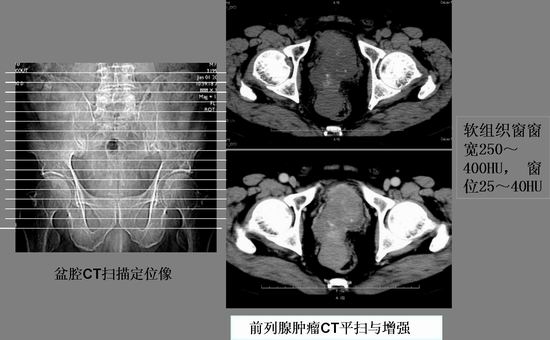

主要功能:全新东芝16层螺旋CT AqullionTM,具有超高分辨率的0.5毫米薄层图像,超长范围的快速扫描和世界上最快的0.40秒全周扫描速度,它代表着当今多层CT较高水平的尖端技术。